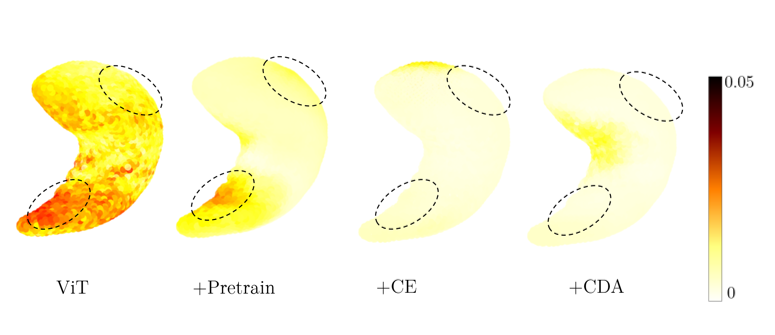

The EU AI Act will put trustworthy AI in the center. This will require handling biases of AI systems. Today, we present our work at #NeurIPS2023 about a new normalization layer in neural networks to effectively reduce bias. neurips.cc/virtual/2023/p… Christian Wachinger Morteza Ghahremani